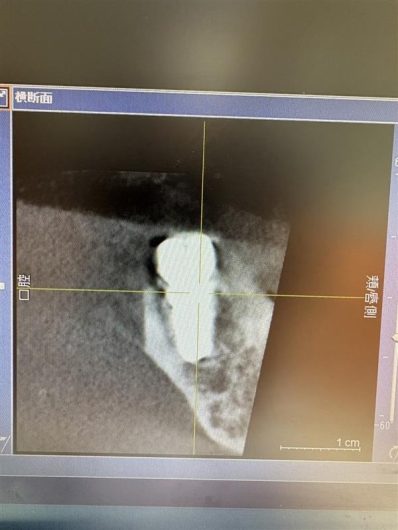

プランニング通り正しい位置に埋める事が出来ました。

骨の状態が良かったので2ヶ月後には型を取りセラミックを入れる事が出来ます。